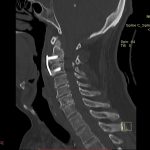

În cazul traumatismelor cranio-cerebrale:

- Diagnosticul traumatismelor de bază de craniu

- Diagnosticul fracturilor:

- Unice

- Multiple

- Cu înfundare

- Complexe cranio-sinusale

- Complexe cranio-etmoidale

- Complexe cranio-orbitare

- Complexe cranio-faciale